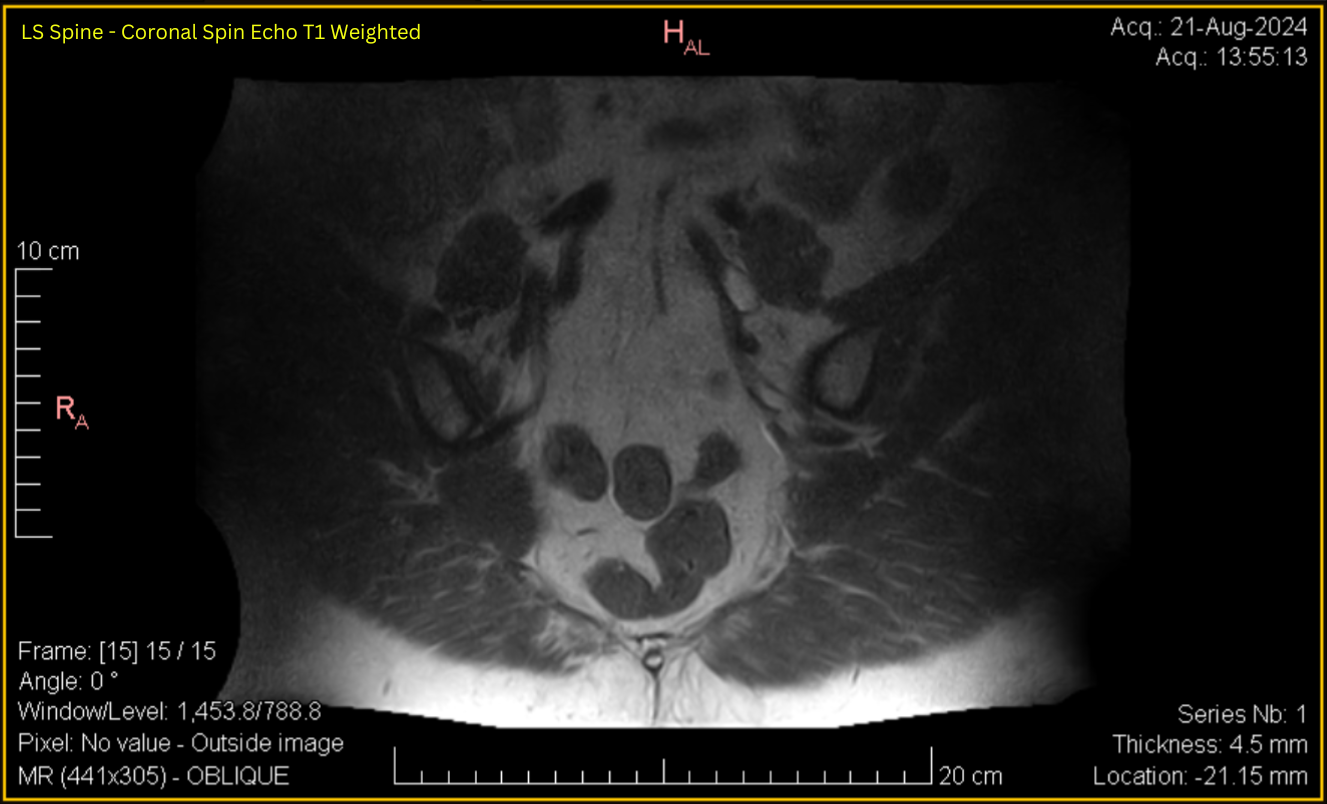

Sacroiliac – Coronal SE T1

LS Spine - Coronal Spin Echo T1 Weighted Oblique (Contrast & brightness adjusted for clarity as below)

See Full DICOM Info and image adjustments

Expand

Click to view full size image